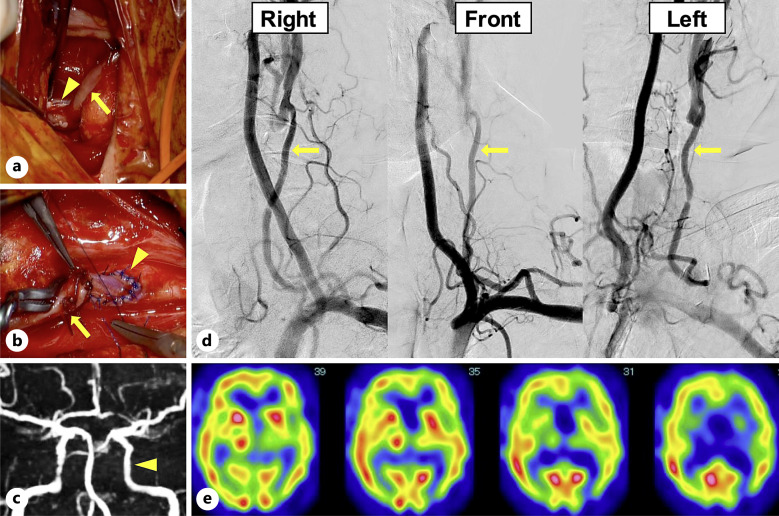

简介:颈总动脉闭塞(CCAO)虽然罕见,但可引起缺血性神经功能障碍,可通过血运重建术治疗。虽然已经提出了几种CCAO旁路入路,但对手术血运重建入路及其功能结局尚未达成共识。在此,我们报告了一例Rile's 1A型CCAO,其中使用桡动脉移植物(RAG)进行锁骨下动脉(SclA)-颈内动脉(ICA)旁路治疗可立即恢复认知功能并成功预防缺血性中风。病例描述:58岁男性,右侧无力反复发作。脑磁共振成像显示多发脑梗死。数字减影血管造影证实左侧CCAO,左侧ICA及同侧颈外动脉无顺行血流。从左巩膜到左颈ICA采用左RAG进行搭桥,巩膜和ICA之间的锁骨上吻合无移植物血管扭结。术后无神经功能缺损,认知功能得到改善。结论:RAG旁路是CCAO的合理治疗选择。CCAO血运重建术可预防缺血性脑卒中,改善认知功能。

Case description: A 58-year-old man presented with recurrent episodes of right-sided weakness. Brain magnetic resonance imaging revealed multiple cerebral infarcts. Digital subtraction angiography confirmed left CCAO and no anterograde blood flow in the left ICA and ipsilateral external carotid artery. A bypass was performed from the left SclA to the left cervical ICA using a left RAG, and supraclavicular anastomosis between the SclA and ICA was performed without graft-vessel kinking. Postoperatively, no neurological deficits were observed, and his cognitive function was successfully improved.

Conclusion: SclA-ICA bypass using an RAG can be a reasonable treatment option for CCAO. CCAO revascularization can prevent ischemic stroke and improve cognitive function.